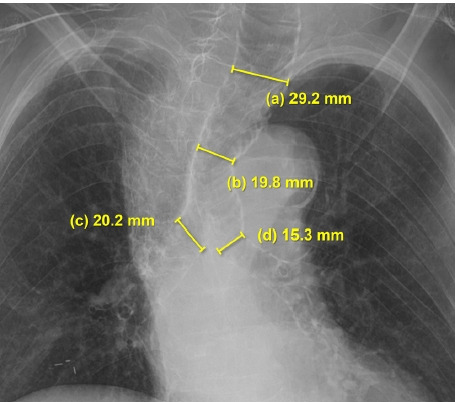

Background: Mounier-Kuhn syndrome (MKS) is a rare disorder characterized by abnormal dilation of the trachea and main bronchi. MKS can be easily missed on chest X-rays, making diagnosis difficult. Under general anesthesia, challenges such as airway leakage or collapse during mechanical ventilation may complicate the achievement of adequate tidal volumes.

Cases: A 94-year-old woman requiring emergency hemiarthroplasty of the hip under general anesthesia was admitted. Preoperative chest X-rays revealed dilation of the trachea and main bronchi, but the patient exhibited no respiratory symptoms. We diagnosed her with MKS and opted for an 8.0-mm-inner-diameter reinforced tracheal tube. We positioned the cuff in the subglottic area, inflating it while monitoring for air leakage. Throughout the surgery, adequate tidal volume was maintained.